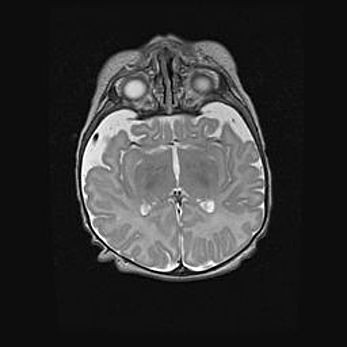

Неполная лизэнцефалия (пахигирия). Открытая гидроцефалия.

Возраст: 17 дней

Вес: 3110 г

Пол: мужской

Окружность головы: 33,5 см

Срок гестации: 35-36 недель

Лизэнцефалия—недоразвитие корковой пластинки и мозговых извилин в результате нарушения миграции нейронов коры. Поверхность мозговых полушарий гладкая. Микроскопически выявляется отсутствие нормальных слоев коры и скопление групп нейронов в подкорковом белом веществе.

Пахигирия—уменьшение числа вторичных извилин. В пораженном полушарии нервные клетки образуют толстый недифференцированный слой с неправильно расположенными нервными волокнами и группами гетеротопных клеток. Нервные клетки незрелые. Белое вещество истончено. При этом нередко аномально развит корково-спинномозговой путь.